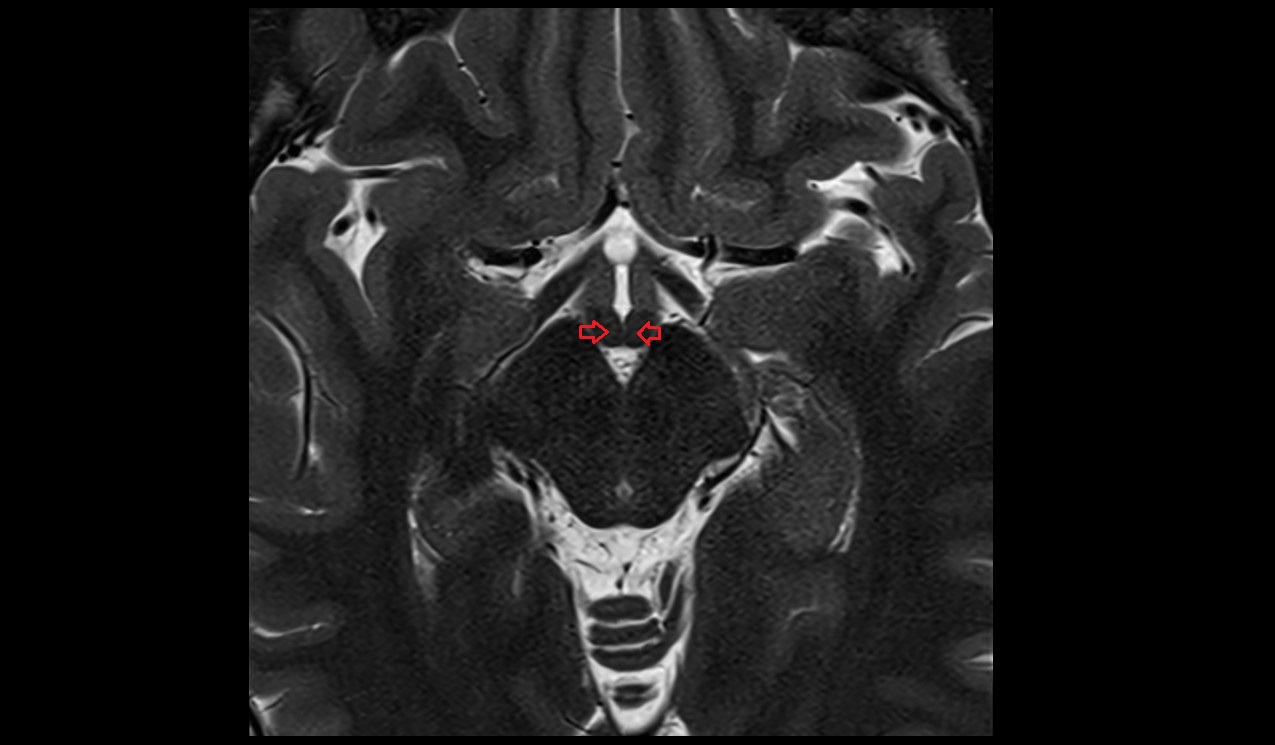

- Optic chiasm

- Pituitary stalk